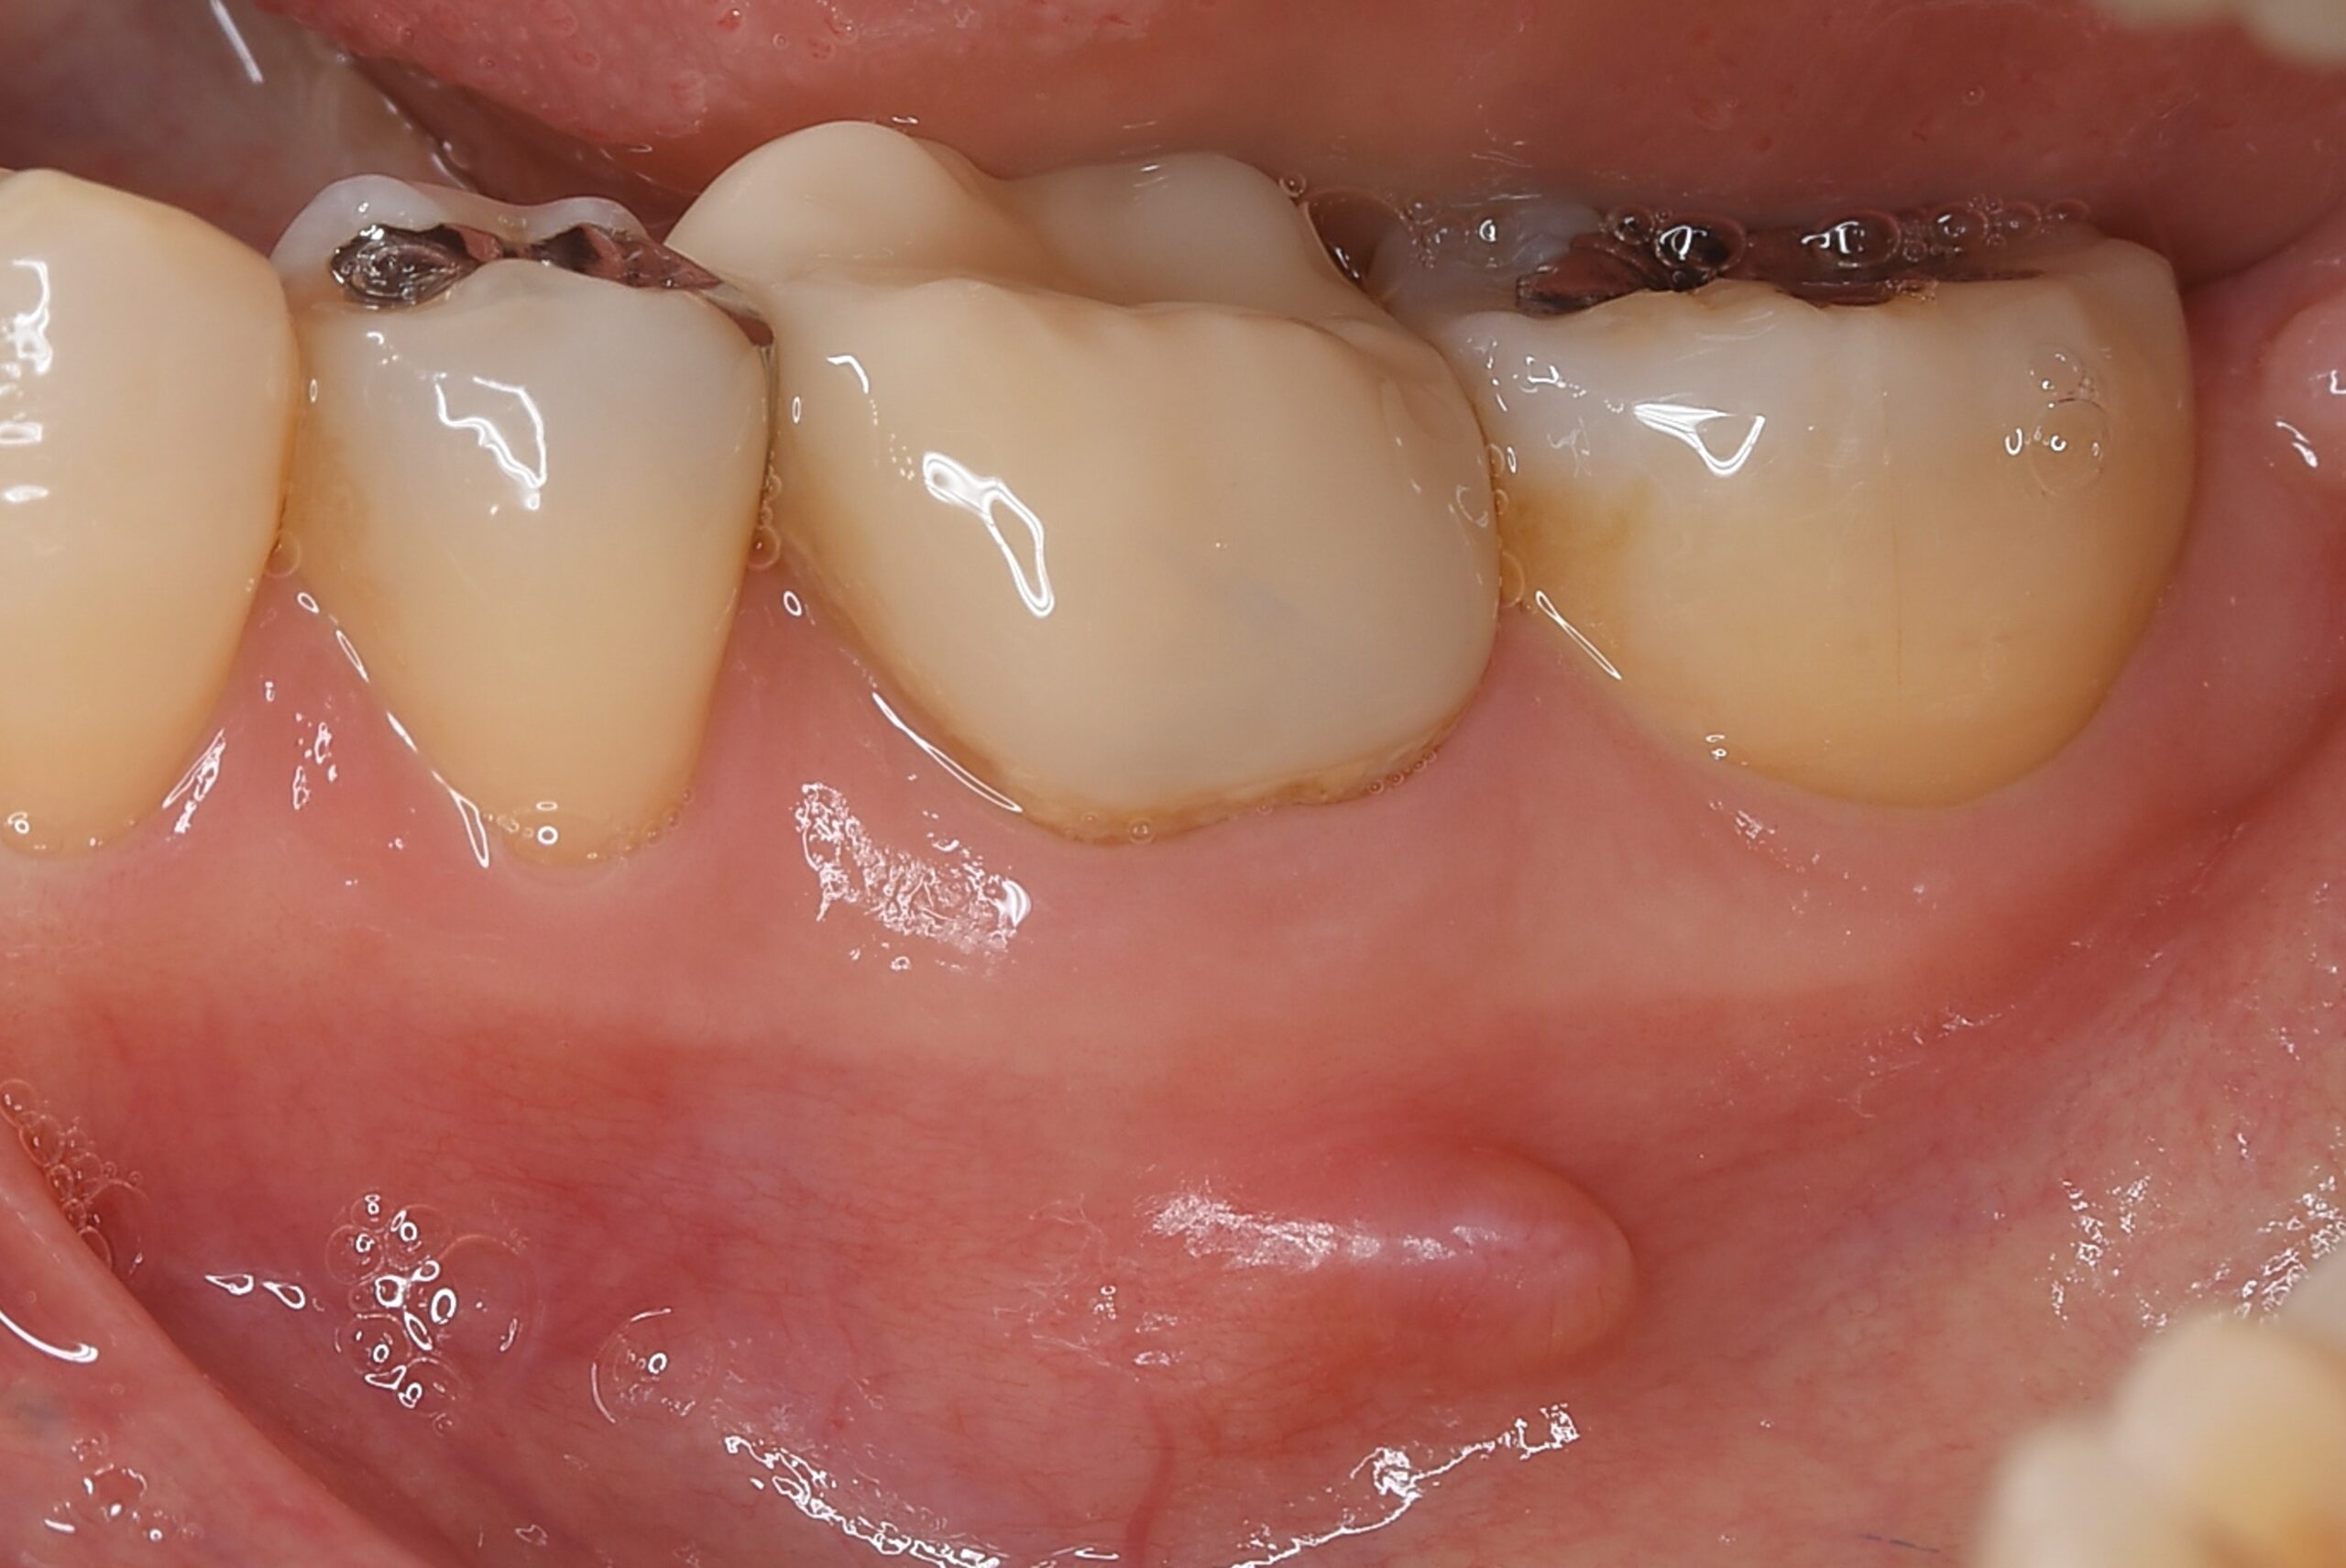

症例3

| 項目 | 詳細 |

|---|---|

| 患者様データ | 50代 女性 |

| 来院時の主訴 | 「左下の歯茎が腫れている。」 |

| 医院の診断 | 慢性根尖性歯周炎 |

| 通院期間 | 4ヶ月 |

| 来院回数 | 6回(定期的なチェック含む) |

| 治療費 | 220,000円(税抜) 《内訳》 精密根管治療80,000円、ファイバーポストコア20,000円、セラミック治療120,000円 |

| リスクと副作用 | ①根管治療歯は長期的には破折するリスク ②メインテナンスが必要 |

| ココがこだわりのポイント☝ |

ラバーダム防湿とマイクロスコープを使用して丁寧に治療を行いました。 |